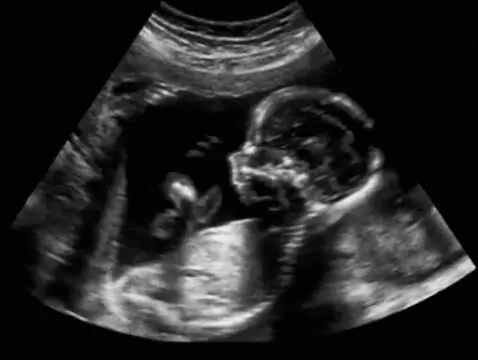

Descubra qué es, cuándo debe realizarse y qué información podemos esperar de un estudio Eco half en este artículo.

Las pruebas prenatales han desempeñado durante mucho tiempo un papel importante en ginecología y obstetricia, pero hoy en día su valor aumenta constantemente debido a que cada vez más mujeres se...